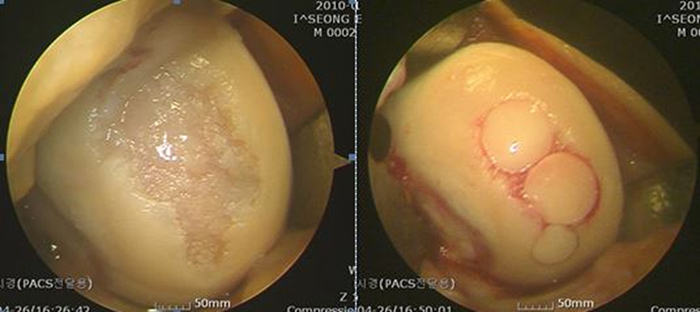

그림 1. 관절 내시경: 석회 침착 및 주변부의 염증 소견

그림 2. 관절경적 석회제거술

그림 3. 석회제거후 남아있는 회전근개의 결손

그림 4. 회전근개 결손에 대해 봉합술 시행